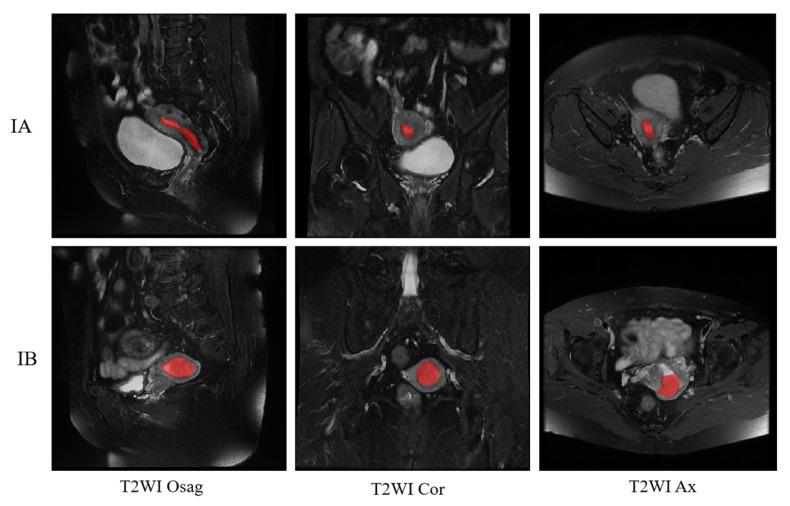

This magnetic resonance imaging multimodal fusion study aims to automate the staging of endometrial cancer using deep learning and to compare the diagnostic performance of deep learning with that of radiologists in the staging of endometrial cancer. This study retrospectively investigated 122 patients with pathologically confirmed early EC from January 1, 2025 to December 31, 2021. Of these patients, 68 were in the International Federation of Gynecology and Obstetrics (FIGO) stage IA, and 54 were in FIGO stage IB. Based on the Swin transformer model and its proprietary SW-MSA (shift window multiple self-coherence) module, magnetic resonance imaging (MRI) images in each of the three planes (sagittal, coronal, and transverse) are cropped, enhanced, and classified, and fusion experiments in the three planes are performed simultaneously. Selecting one plane for the experiment, the accuracy of IA and IB classification was 0.988 in the sagittal, 0.96 in the coronal, and 0.94 in the transverse position, and classification accuracy after the fusion of three planes reached 1. Finally, the automatic classification method based on the Swin transformer has an accuracy of 1, a recall of 1, and a specificity of 1 for early EC classification. In this study, the multimodal fusion approach accurately classified early EC. It was comparable to what a radiologist would perform and simpler and more precise than previous methods that required segmenting followed by staging.

这项磁共振成像多模态融合研究旨在利用深度学习实现子宫内膜癌分期的自动化,并比较深度学习与放射科医生在子宫内膜癌分期方面的诊断性能。本研究回顾性调查了2021年1月1日至2025年12月31日期间122例经病理证实的早期子宫内膜癌患者。其中,68例为国际妇产科联盟(FIGO)IA期,54例为FIGO IB期。基于Swin变压器模型及其专有的SW-MSA(移位窗口多重自相干)模块,对矢状面、冠状面和横断面三个平面的磁共振成像(MRI)图像进行裁剪、增强和分类,并同时在三个平面上进行融合实验。选择一个平面进行实验,矢状面IA和IB分类的准确率为0.988,冠状面为0.96,横断面为0.94,三个平面融合后的分类准确率达到1。最后,基于Swin变压器的自动分类方法对早期子宫内膜癌分类的准确率为1,召回率为1,特异性为1。在本研究中,多模态融合方法准确地对早期子宫内膜癌进行了分类。它与放射科医生的表现相当,并且比以前需要先分割再分期的方法更简单、更精确。